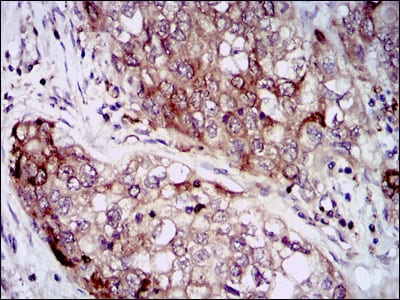

分类: 科研抗体货号: 30368别名: NOS; INOS; NOS2A; HEP-NOS应用: WB,IHC,FCM反应种属: Human,Mouse,Rat,Monkey